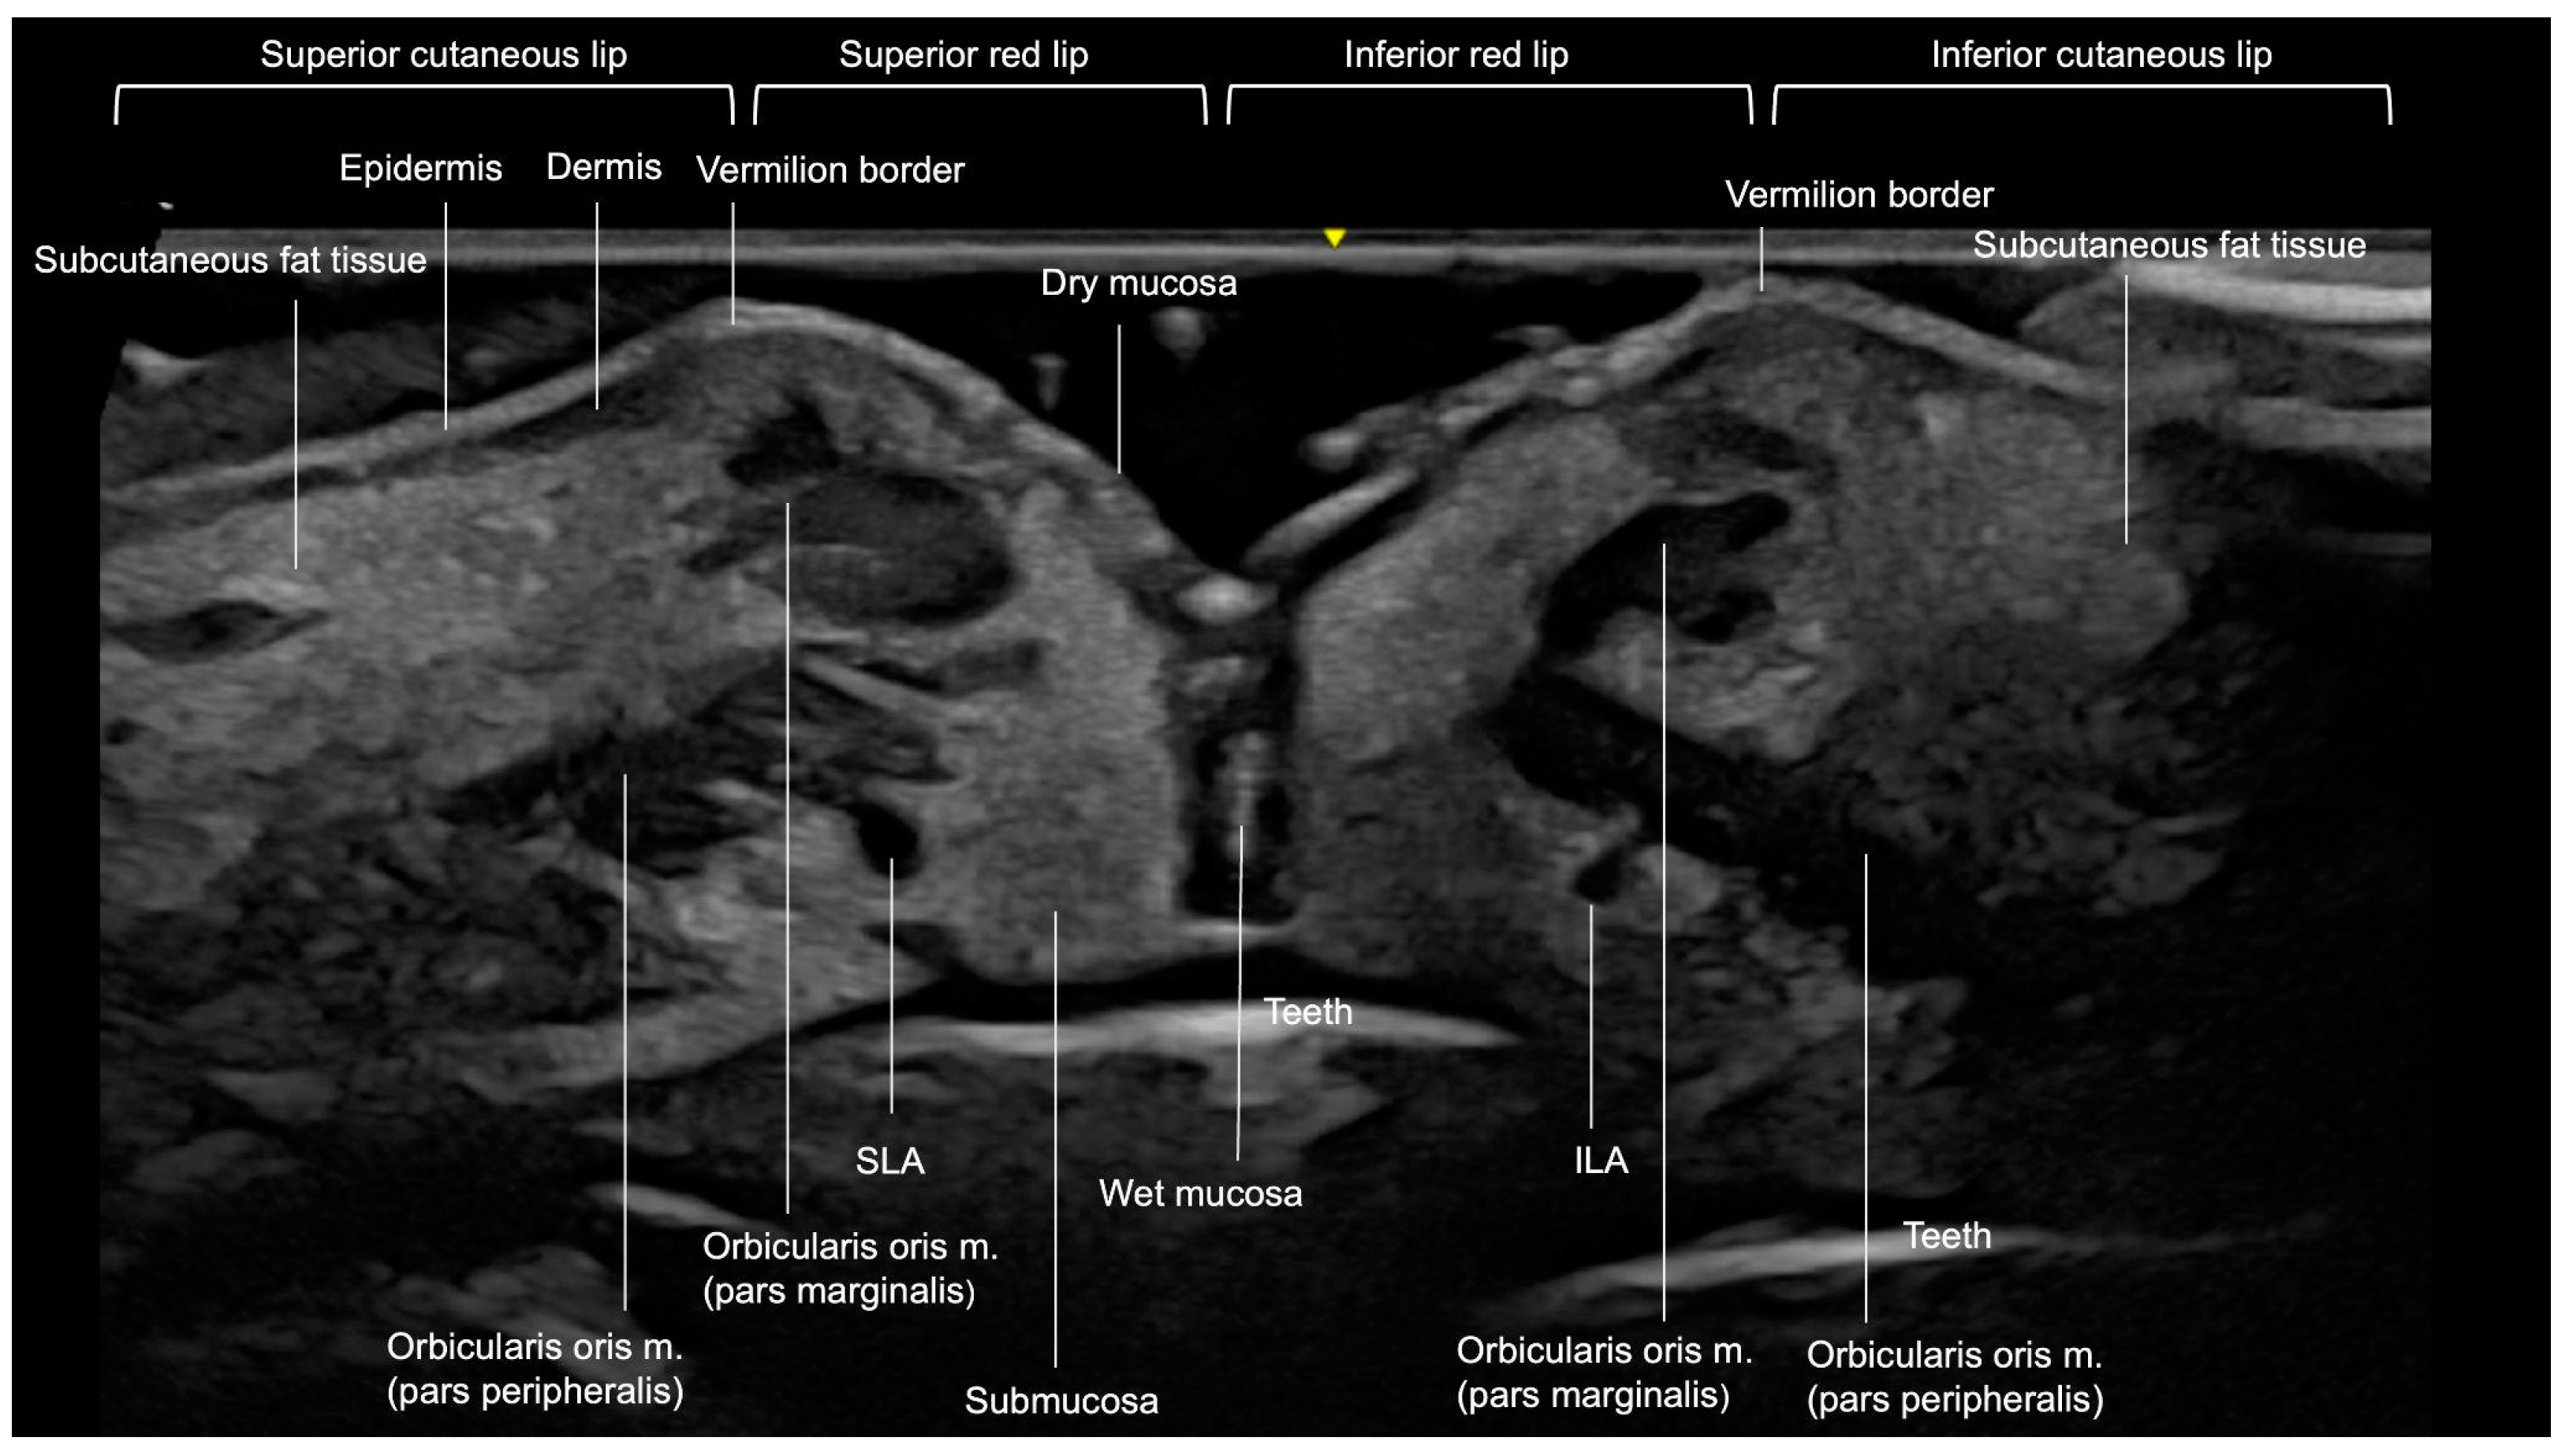

3.3. Lips

3.3.1. Sonographic Anatomy

3.3.2. Ultrasound-Guided Filling Techniques of the Lips

- Filling of the Cutaneous Lip

- Filling the vermilion of the lip

- In general, lip filler techniques can be categorized based on the following:

- Injection method: cannula or needle;

- Injection depth: superficial (below the dry mucosa) or deep (submuscular);